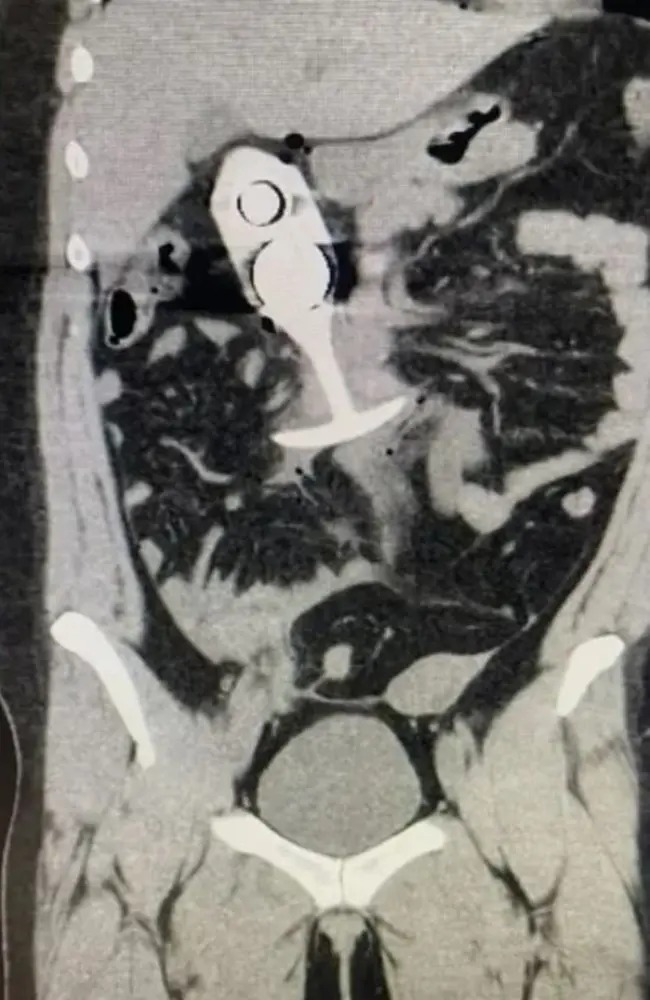

虽然这宗事件发生在2023年4月,但据称显示患者事发后扫描的图象,最近开始在网上流传,提示人们不要在扫描期间佩戴任何金属物品。

有关内容进一步声称,塞子以「声速」从患者的直肠被拉到胸腔,受创者幸存下来,但伤势严重。